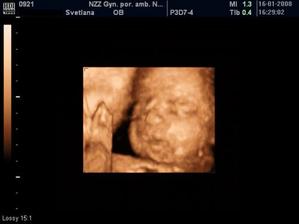

Sophie a veci okolo nej..ako ide cas a co sa deje

Mix fotiek 🙂